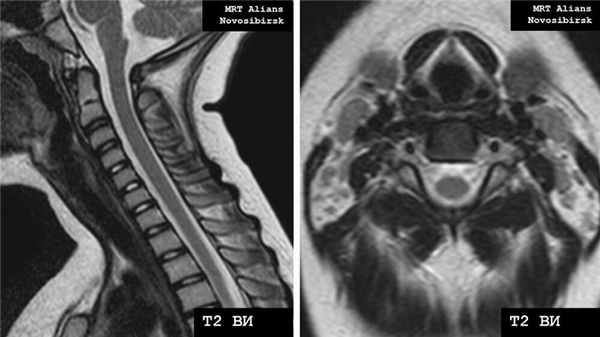

Рис. 1. МРТ шейного отдела позвоночника (норма).

Рис. 2. МРТ шейного отдела позвоночника (дорзальная экструзия /грыжа/ межпозвонкового диска С5/6).